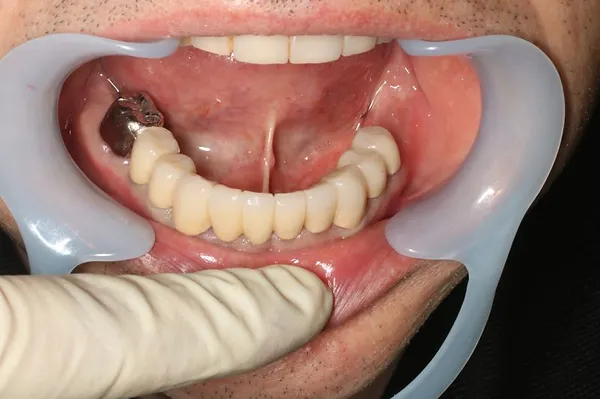

6入れ歯にしないブリッジ治療【ケース1】

H20.6.2のレントゲン

歯槽膿漏の為、上の6本の歯を抜き、上の右端から左端まで繋げたブリッジを作りました。

H31.1.25のレントゲン

H21.2.21に上の歯(ブリッジ)が完成しました。

左の写真は10年ちょっと経過したH31.1.25日に撮影した写真で、経過良好と思われます。

下顎も虫歯と歯槽膿漏のため長く持たせるために左下奥歯の一本を抜歯し残りを繋げて作りました。